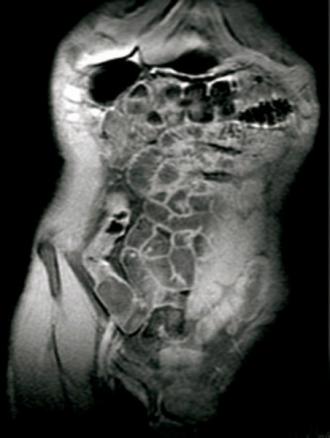

Entéro-IRM. Prise de contraste de la dernière anse iléale qui apparaît en hyper-signal T1 avant injection de gadolinium.